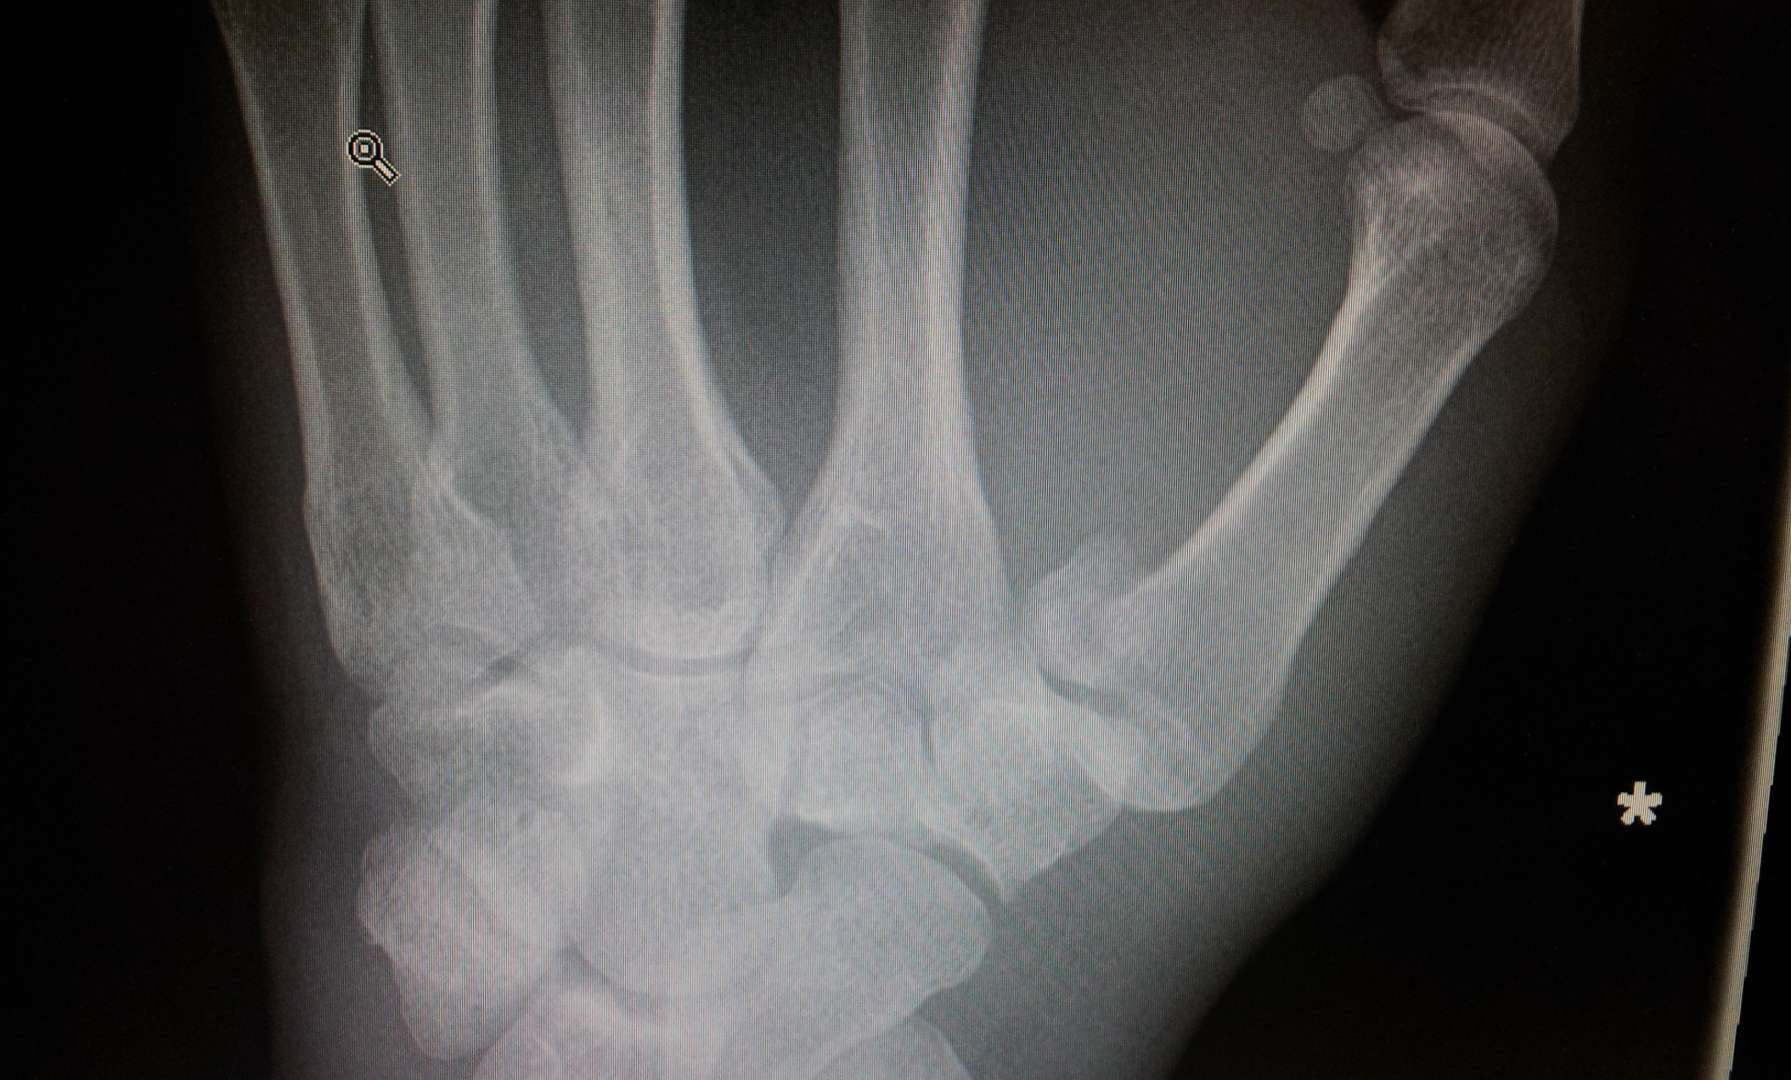

Did mine last night coming off bike hard on some acorns in the woods. Minor injury clinic was great. In Xray plaster cast and out in under an hour. Now awaiting hand-clinic appointment to see if it needs pinning (likely by all accounts).

Anyone had one of these and if so what is the likely outcome? How long out of action. It is my right hand too which is a pain and makes my job near impossible!

Did mine in mid-September 2014. Bennetts fracture. Broke it on the Saturday*, surgery on the Tuesday. Two pins to keep my thumb in place. Around 6 weeks in plaster. Non-dominant hand so still managed to wipe my own arse. Back at work a couple of days later. Looking back at Strava, my first ride back was commuting after 8 weeks and I remember that being sore, no proper MTB ride until the festive break (approx 12 weeks post injury). Hand remained swollen for ages afterwards and I still have a (very) small bit of restricted movement now - natural resting position for of thumb is it sticks out a bit more than before. Feels tighter even now if I stretch my thumb tip over to touch my pinkie, for example.

September last year on a rooty off piste trail at Grizedale. (I remember Bennett’s but not 100%). Lots of worrying comments about possible surgery if it didn’t go back together well, after cast. But actually just under 6 weeks in plaster and then “be careful for a while but just start using it normally “